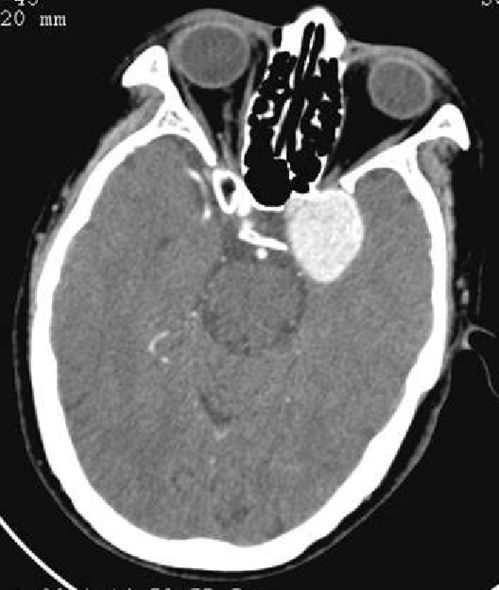

每位宝宝的心脏发育情况都是独特的。一些常见的异常情况包括先天性心脏病,如室间隔缺损等。一些轻微的结构异常有可能在一岁内自愈,但严重的病例可能需要手术治疗。孕期筛查是提前发现心脏畸形的关键手段,胎儿心脏彩超在孕期的第20至24周是筛查的黄金时期。新生儿出现喂养困难、呼吸急促、发绀等症状时,应及时就医排查。